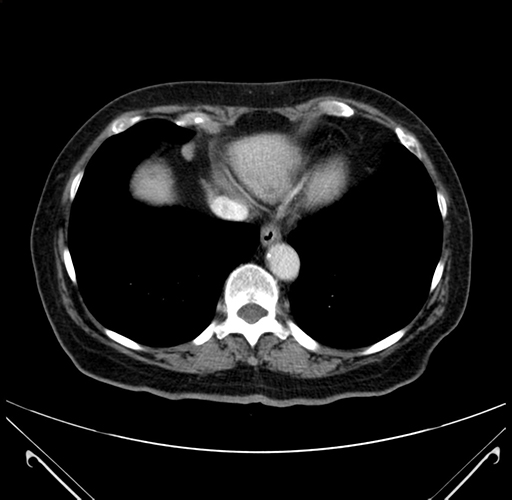

Pre-Chemo: Axial Venous